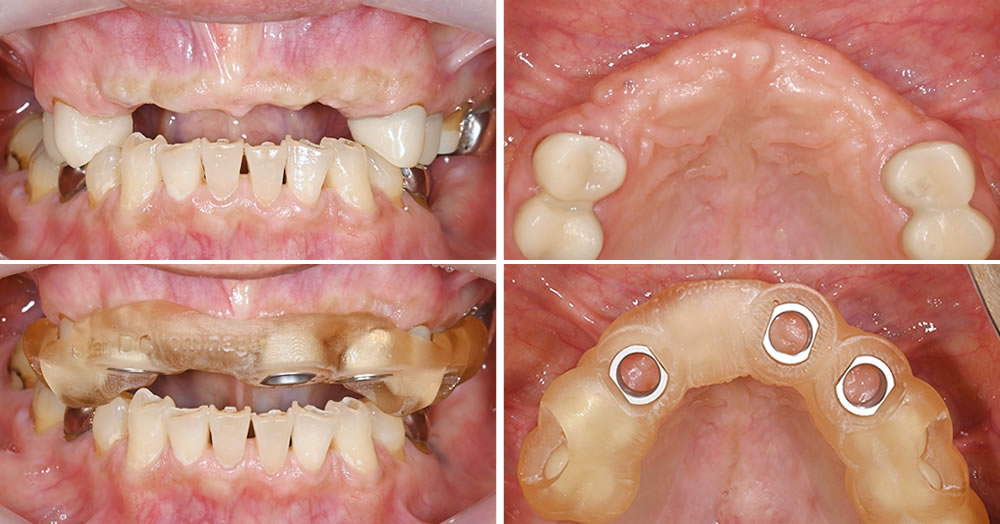

上顎前歯は保存が困難であったため抜歯を行い、前歯部分の治療に加えて全顎的な包括治療を行う方針となりました。上顎前歯部にはインプラント治療を計画し、サージカルガイドを用いてインプラント埋入手術を実施していきます。

歯肉を剥離し、インプラントを埋入した状態です。設計されたサージカルガイドとズレが生じないよう、精密な処置を行いました。